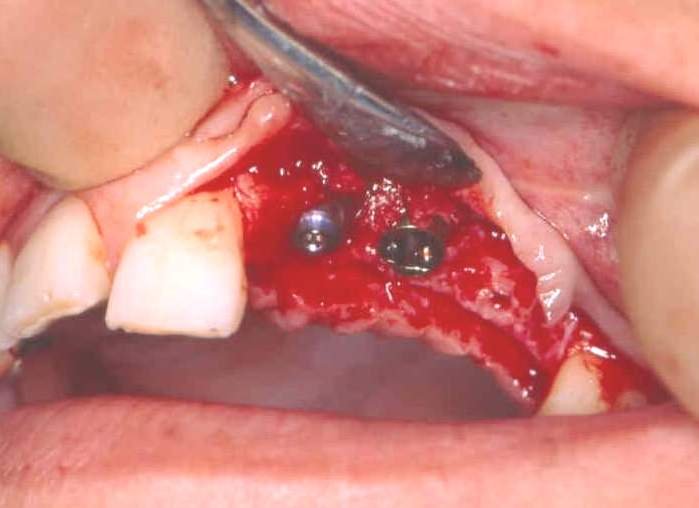

It is essential to avoid contamination of the pure titanium surface of the implant with stainless steel instruments or soft tissue. The implant is screwed into the bone at slow speed until the maximum torque is reached. Over-tightening can strip the implant from the bone. Sometimes exposed threads are seen on the buccal/labial aspect of the implant on final placement. If there is primary stability, the majority of implants will integrate despite exposed threads (Figure 8).

Figure 8: Implant socket preparation.

These threads can also be covered by bone harvested by a surgical filter or bone substitute. Semipermeable membrane covering this can promote healing by guided tissue regeneration (Figure 9). A cover screw is fitted over the internal threads of the implant (Figure 10) and the wound closed. The patient is advised not to wear their prosthesis for 7 to 10 days, followed by occasional wear only.

Figure 10: Dental implants in place with cover screws visible.